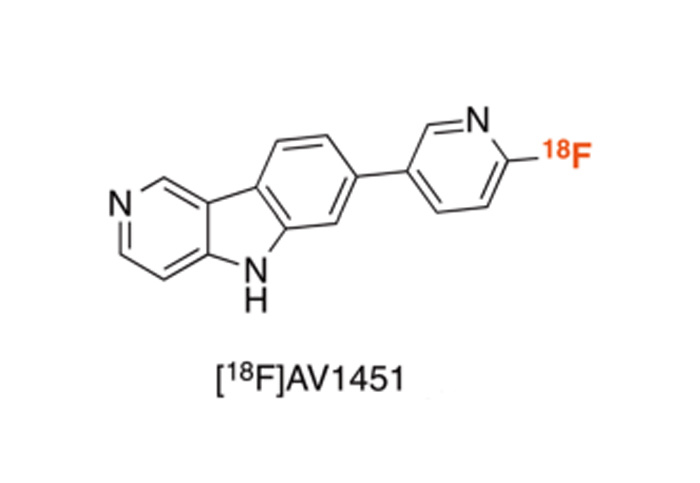

對(duì)18F、11C、68Ga、等核素示蹤劑的(de)合成與國(guó)外(wài)主流示蹤劑合成平台達到(dào)同一(yī)水(shuǐ)<平;